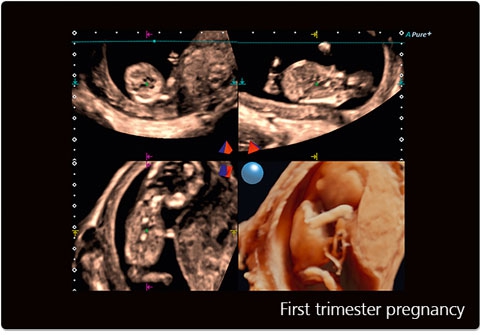

• STIC - исследование сердца плода в режиме объёмной визуализации

• 3D Color - цветное 3-х мерное изображение

• STIC Color - цветная объёмная визуализация сердца плода

• Трехмерная эхография в реальном времени с использованием специализированных 4D датчиков;

• Программа анализа сердца плода в трех проекциях в реальном времени 4D Stick;